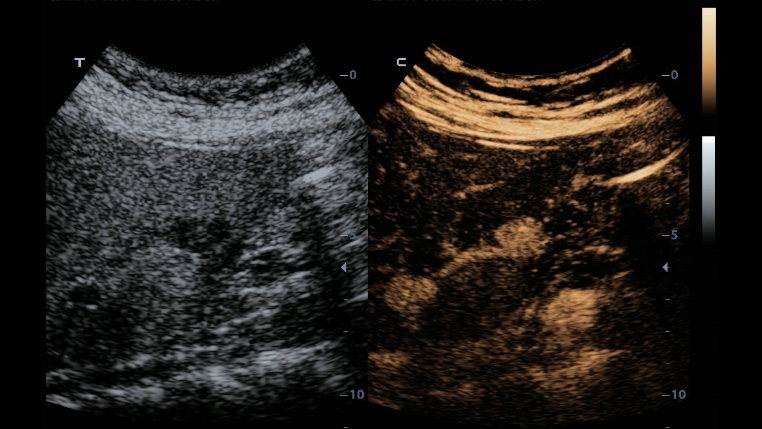

Hervorragende Detailaufl?sung

Unsere Motivation bei Mindray ist es, die moderne Medizintechnik durch zukunftsorientierte Techno-logien zu verbessern. Mit seinem Full HD-Monitor, bew?hrten Ultraschalltechnologien und einer optimierten Schallkopf-Familie bietet das DC-40 mit Full HD eine hervorragende Bildqualit?t. Sie verbessert ein breites Spektrum klinischer Anwendungen.

Diese bew?hrten Ultraschalltechnologien sorgen f├╝r eine h?here Diagnosequalit?t:

- iClear (Rauschunterdr├╝ckungs-Technologie)

- PSH (Harmonic Imaging mit Phasenverschiebung)

- iBeam: (Spatial-Compounding)

Der Einsatz anerkannter Bildgebungstechnologien macht das DC-40 mit Full HD sehr leistungsstark und hochwertig. Sie sind erfolgreich aus etablierten Ultraschallsystemen migriert worden. Eine clevere Kombination von Ultraschallsonden mit spezialisierten Schallk?pfen unterst├╝tzt erstklassige Ergebnisse in einem breiten Anwendungsspektrum. Mit Hilfe der Breitband-Schallk?pfe l?sst sich eine Vielzahl an Patiententypen erfolgreich untersuchen.